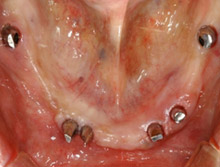

術前の下顎の様子。

下顎は6本のインプラント植立し、ブリッジタイプの補綴をいれます。

下顎へブリッジを装着した状態